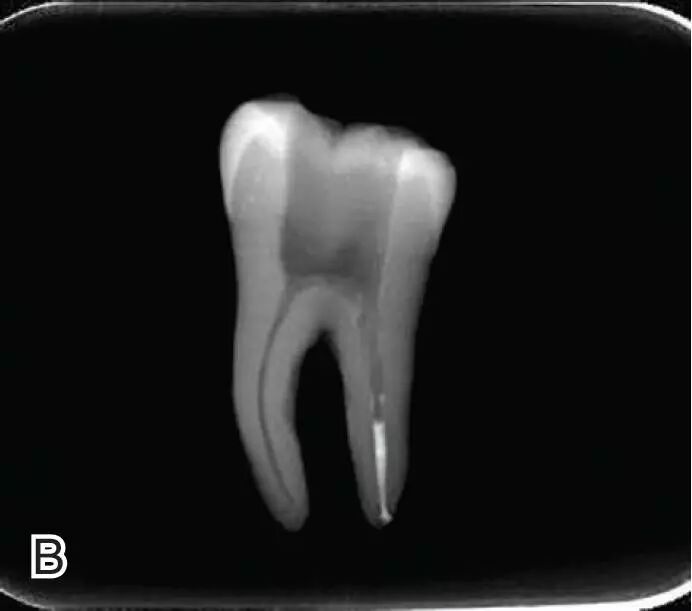

热牙胶根中上段的充填

在完成根尖段的充填后,使用热塑牙胶注射仪对根管中上段进行分层充填,一般分2~3次完成充填,每次充填均使用相应直径大小的垂直加压器进行加压。拍片确认充填效果。